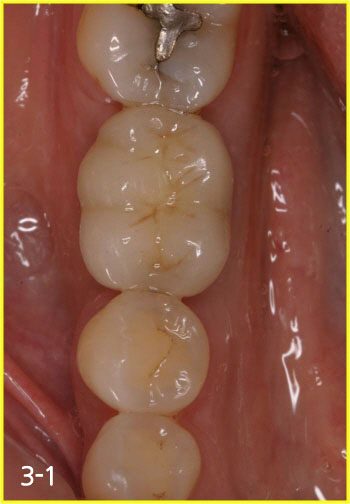

taking X-ray to secure safe implant surgery

Placing implant in bone graft site